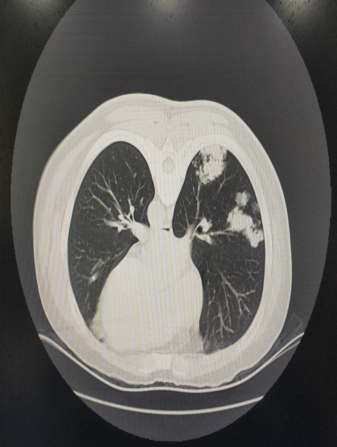

近日,省中医院肺病科联合影像科为一例双肺多发肺结节患者实施“电磁导航CT引导下肺结节穿刺活检术”。该手术是我院首例使用实时电磁导航设备CT引导下肺结节穿刺活检术,精准、快速、安全的为肺结节患者的诊断开辟了高效、安全的新路径。

该例患者为一个宁夏回族自治区的开朗小伙子,此次因泌尿系结石在某医院查胸部CT时发现双肺多发团块样、结节样高密度影,高度怀疑为肺恶性肿瘤。患者经当地医生推荐慕名前来我院寻求中西医结合诊治。经肺病科马战平主任及谭国超副主任充分评估病情后,决定联合影像科对该患者实施“电磁导航CT引导下肺团块、结节穿刺活检术”。术前经科室的充分讨论及相关设备的准备并在我院影像科刘国庆主任团队的全力配合下,为患者顺利完成了此次肺活检手术。患者术后恢复良好。

术前